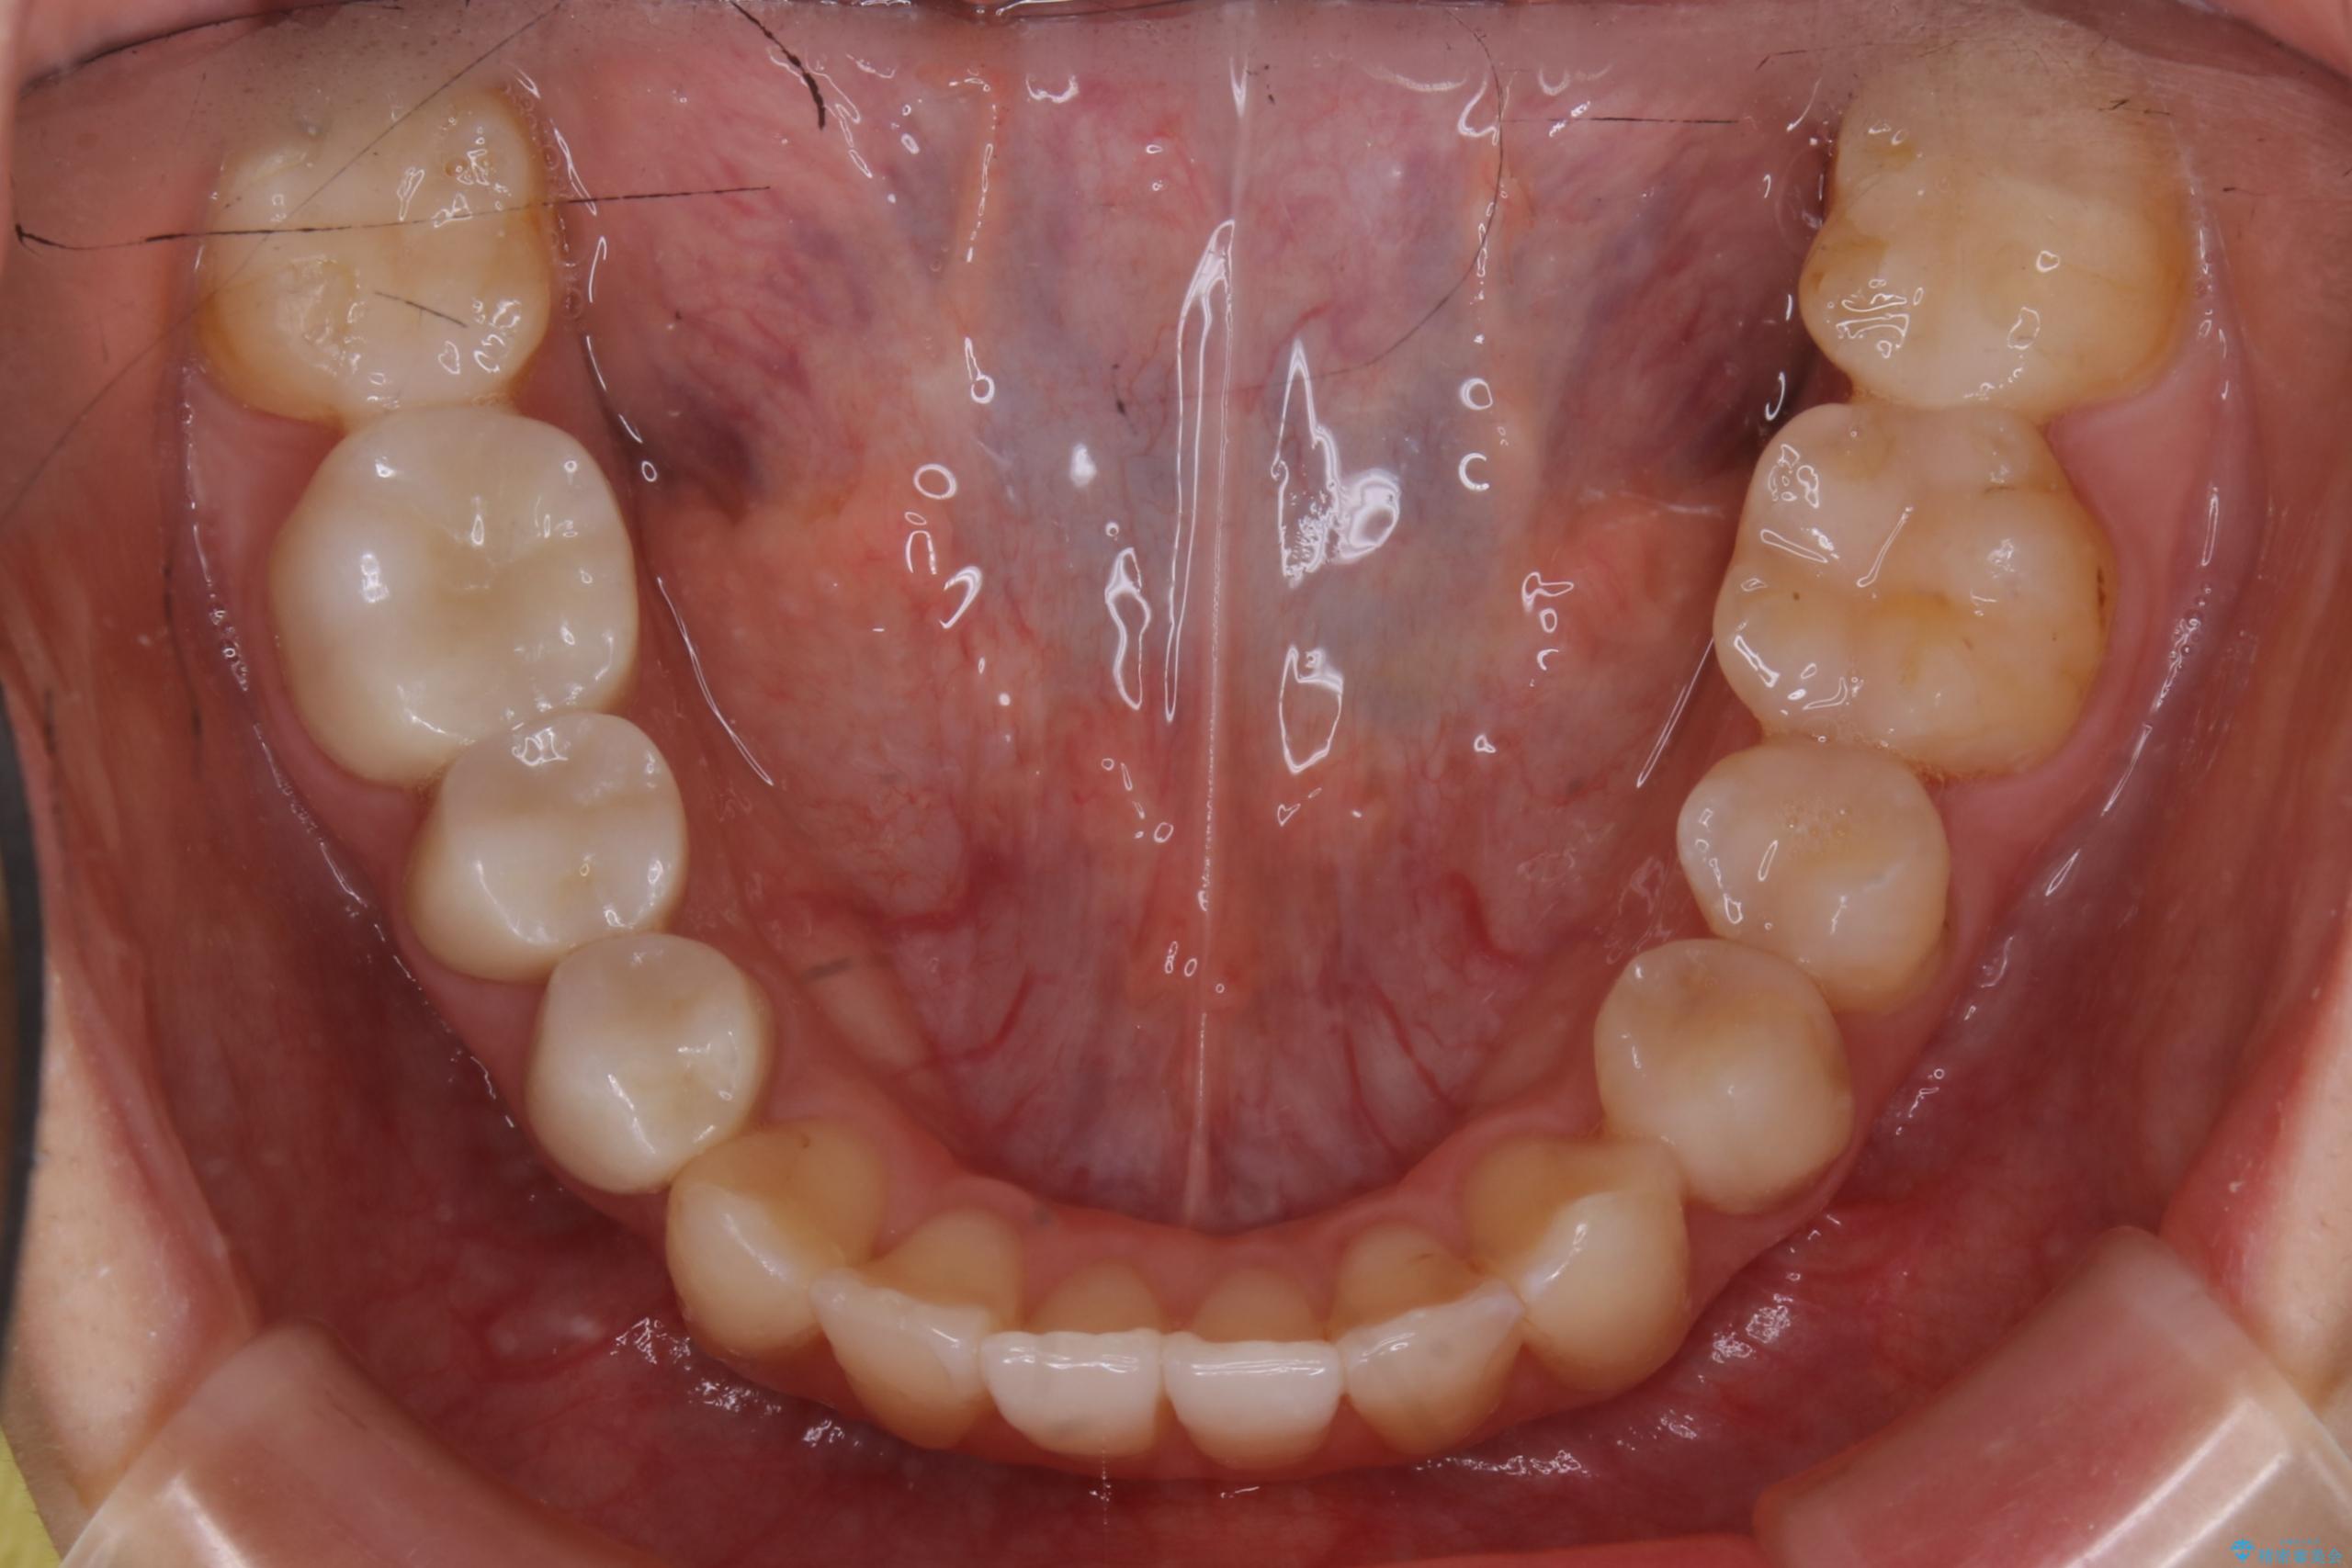

治療後

20代 女性 非抜歯で歯列をコンパクトに20代 女性 非抜歯で歯列をコンパクトに20代 女性 非抜歯で歯列をコンパクトに